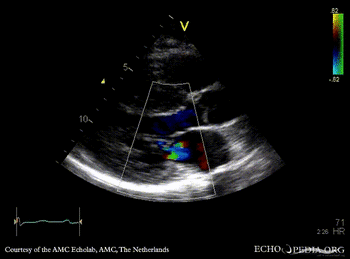

E00513.gif E00514.gif

PSAX: severe concentric hypertrophy of left ventricle PLAX with Color Doppler: high velocity turbulent flow in LVOT, moderate mitral regurgitation